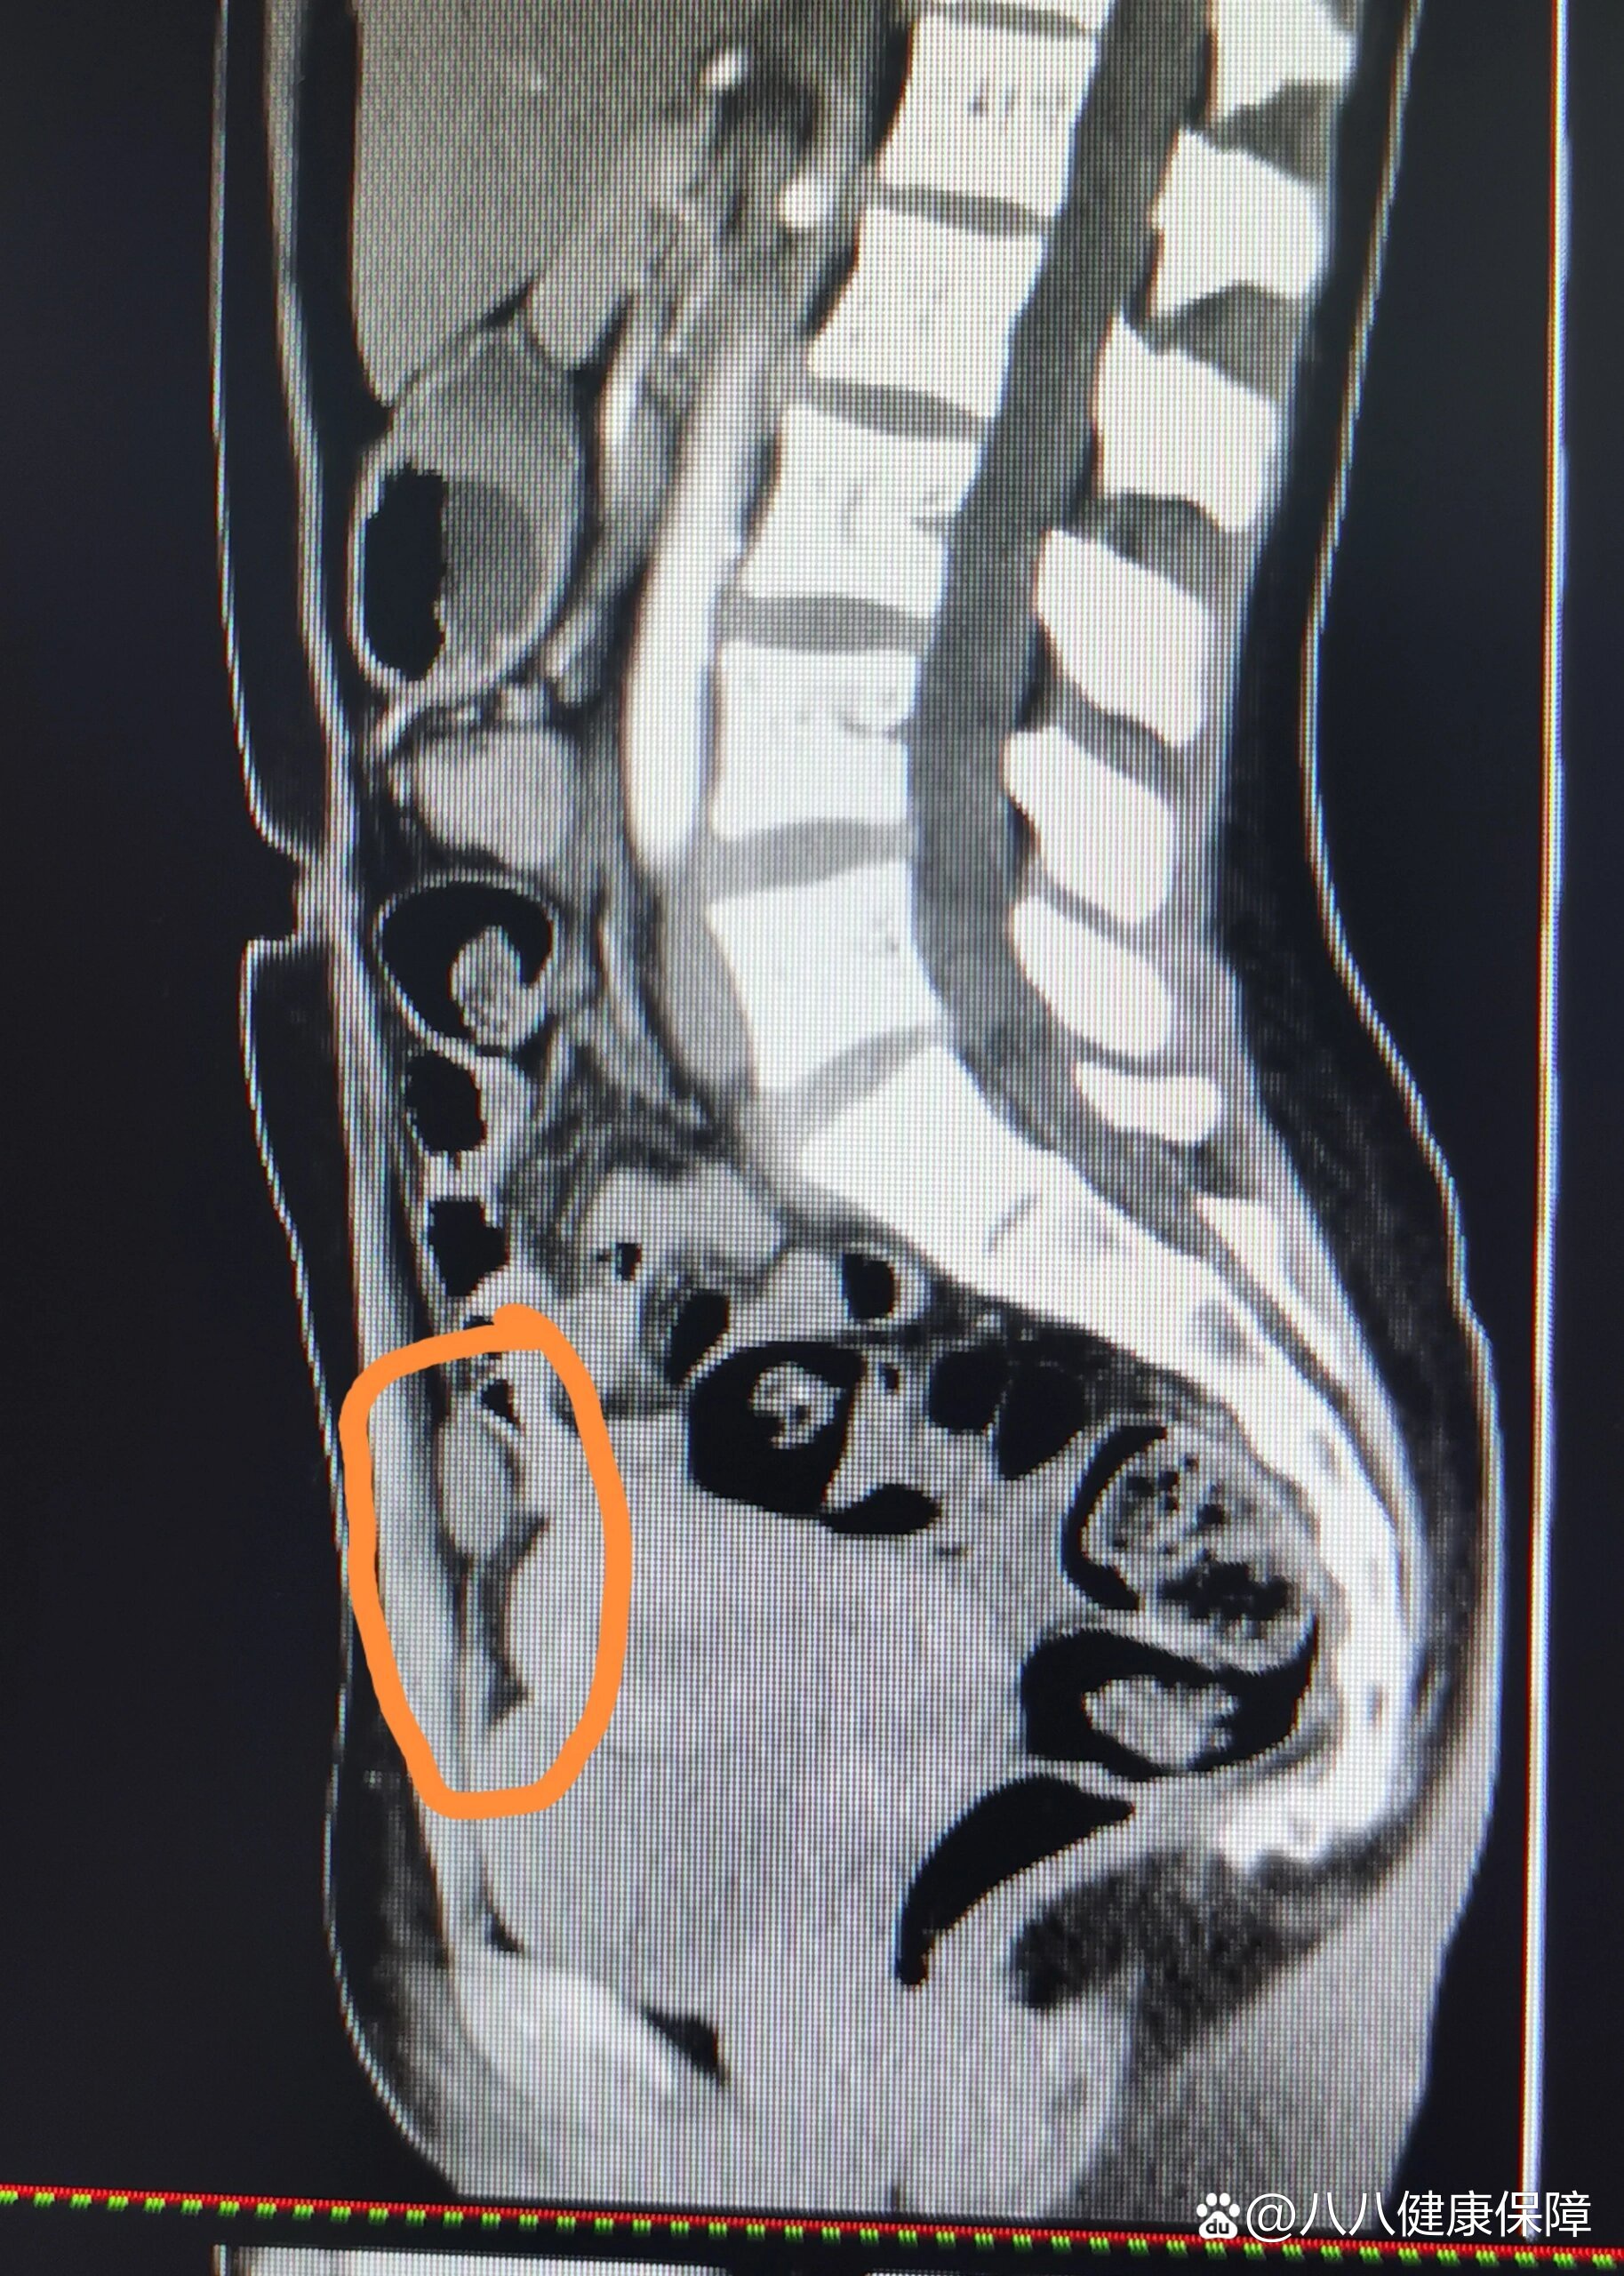

分享比较罕见的成年人脐尿管瘘

图片尺寸4032x3024

脐尿管瘘相对少见,就是脐部与膀胱之间有异常通道连接,表现为脐部反复